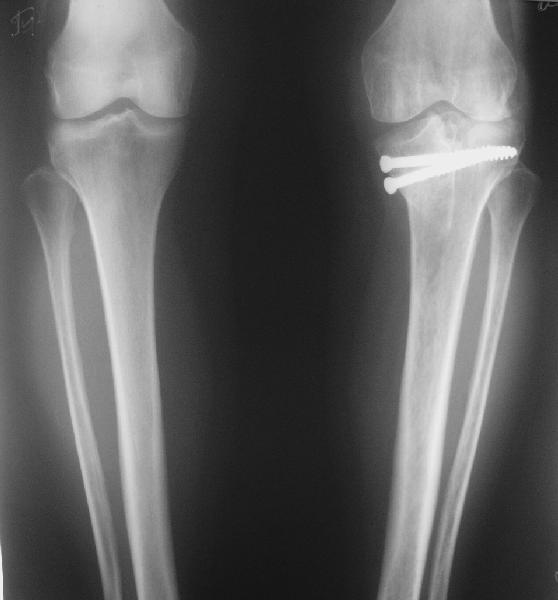

В отделение поступила пациентка из области, 68 лет. Травму получила год назад, находилась на лечении в ЦРБ по поводу перелома внутреннего мыщелка большеберцовой кости, была вот так прооперирована. На сегодняшний момент беспокоят боли в области коленного сустава при ходьбе, движения ограничены, от 180 до 100. При планировании операции возникли разногласия, на каком уровне делать остеотомию. То ли поднимать внутренний мыщелок, т.е. делать остеотомию через сустав, то ли обойтись внесуставной коррекцией оси. Второй вариант менее травматичен, но конгруэнтность сустава при этом останется нарушенной, улучшится только ось конечности. Допустима ли такая коррекция, или все-таки правильнее не менять взаимоотношения наружного мыщелка с диафизом, а поднять именно внутренний мыщелок?

По снимку видно, что и в наружном отделе сустава есть серьезные изменения.